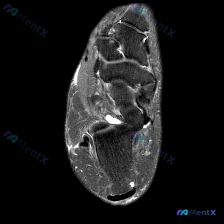

看到一个有意思的踝关节病例,临床怀疑软骨异常,但单张MRI影像的表现和临床判断有矛盾,整理一下思路和大家分享。 一、现有病例与影像信息 本次提供的是踝关节MRI-T2序列轴位单张图像,已完成初步影像分析: 1. 影像基本表现: - 可见踝关节间隙及距下关节周围明显高信号积液影,提示关节腔内积液 -...